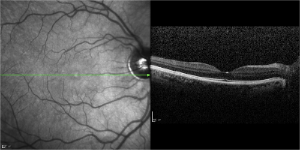

Digital Infrared and Red-Free Imaging

Digital infrared imaging is a variation of fundus photography. Using a longer wavelength of light makes it possible to detect structural details of the retina, which may not be detected under visible light. Digital red-free imaging creates images, which highlight specific structures in the nerve fiber layer by using a blue wavelength of light to illuminate the retina.

Digital infrared and red-free imaging are performed in the office at the retina center vienna.